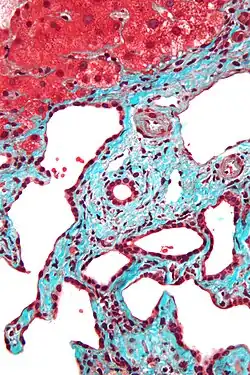

Micrograph of a bile duct hamartoma. Trichrome stain, high magnification -

Histopathology of a bile duct hamartoma, high magnification, H&E stain. It shows typical features of bile duct hamartoma: Small to medium sized, irregularly shaped bile ducts lined by bland cuboidal epithelium (may also be flattened). Prominent intervening collagenous stroma. Bile ducts containing eosinophilic debris (may also contain inspissated bile) -